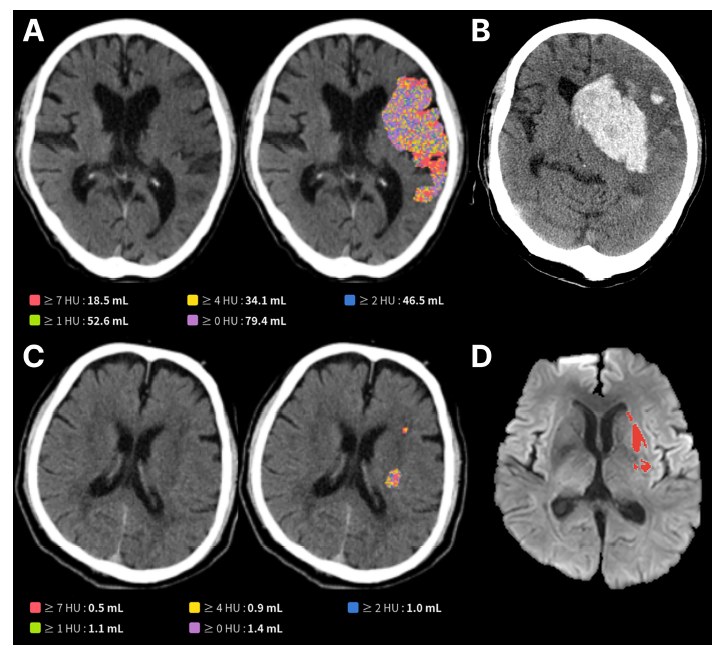

제이엘케이의 AI 모델은 이러한 문제를 해결하기 위해 개발됐다. 다수의 뇌경색 환자 NCCT와 확산강조영상(DWI) 데이터를 학습한 딥러닝 기술을 기반으로, 육안 식별이 어려운 뇌 손상 영역을 자동 검출하고 그 부피를 정량적으로 분석할 수 있다.

그 결과 AI가 NCCT 영상에서 분석한 뇌 손상 부피가 클수록 3개월 후 환자의 기능 회복 가능성은 현저히 낮았으며(50mL 초과 시 17.3% vs. 54.2%), 뇌출혈 전환과 같은 심각한 합병증 발생률은 더 높게 나타났다(66.0% vs. 46.3%). 이는 응급실에서 촬영한 기본 CT만으로도 환자의 장기적인 예후를 예측할 수 있음을 보여주는 중요한 과학적 근거다.